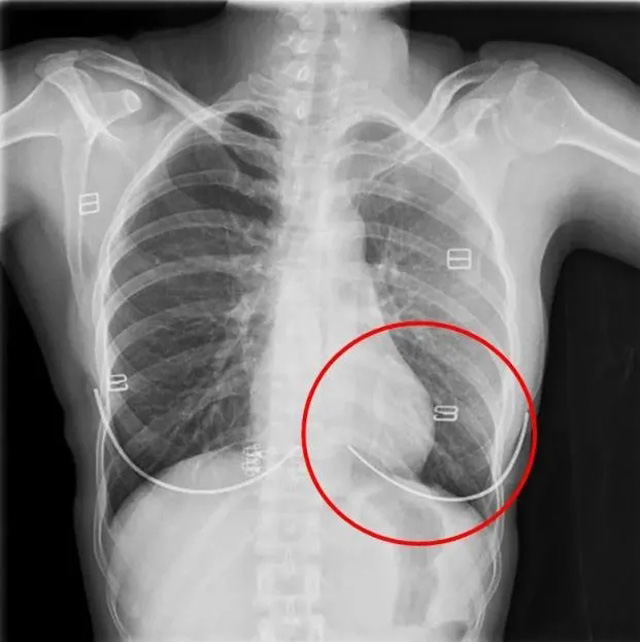

DR是一種比較常規(guī)的基礎(chǔ)影像學(xué)檢查方式,適用于人體各部位的健康普查及疾病檢查等優(yōu)勢(shì),在臨床基礎(chǔ)檢查中備受醫(yī)生和患者的青睞。DR體檢車在健康體檢中有著非常重要的地位,由通過電纜串接在一起的探測(cè)板、掃描控制器、系統(tǒng)控制及影像顯示器等構(gòu)成。對(duì)比CT檢查而言,DR檢查的價(jià)格更低,輻射劑量更小它可以讓疾病預(yù)防,微細(xì)病變可更好顯示診斷治療提供科學(xué)的結(jié)果依據(jù)。很多外傷患者都要做DR檢查,來判斷是否骨折或其他的情況。體檢過程中面對(duì)DR體檢車做檢查時(shí)候需要準(zhǔn)備注意什么呢?很多時(shí)候大家都有這樣的疑問,身上攜帶的物品是否會(huì)對(duì)圖像造成遮擋或給機(jī)器帶來干擾?檢查前如何準(zhǔn)備才不會(huì)影響檢查準(zhǔn)確性?

首先需要穿比較寬松的衣物,不要戴金屬的飾品。還可以用醫(yī)院的衣服,胸圍的也要脫掉,因?yàn)橛袖撊?。不然的話這些金屬飾品會(huì)干擾檢查圖像的清晰度,引發(fā)誤診或者漏診。半年內(nèi)需要備孕懷孕的人士,應(yīng)慎重或盡量避免放射線照射就需要跟醫(yī)生講,幼兒、年老體弱、危重患者,家屬應(yīng)有效配合醫(yī)生完成檢查;對(duì)不用檢查的部位做好防護(hù)工作。在DR已經(jīng)開始運(yùn)作時(shí)候,檢查進(jìn)行中的提示燈亮了,不要推開檢查室大門跟勿隨意進(jìn)入,不然會(huì)受到輻射。按照醫(yī)生的要求保持好體位。曝光時(shí)候不動(dòng)平靜均勻呼吸時(shí)屏氣,避免產(chǎn)生運(yùn)動(dòng)偽影這樣才能保障圖像的高清準(zhǔn)確。